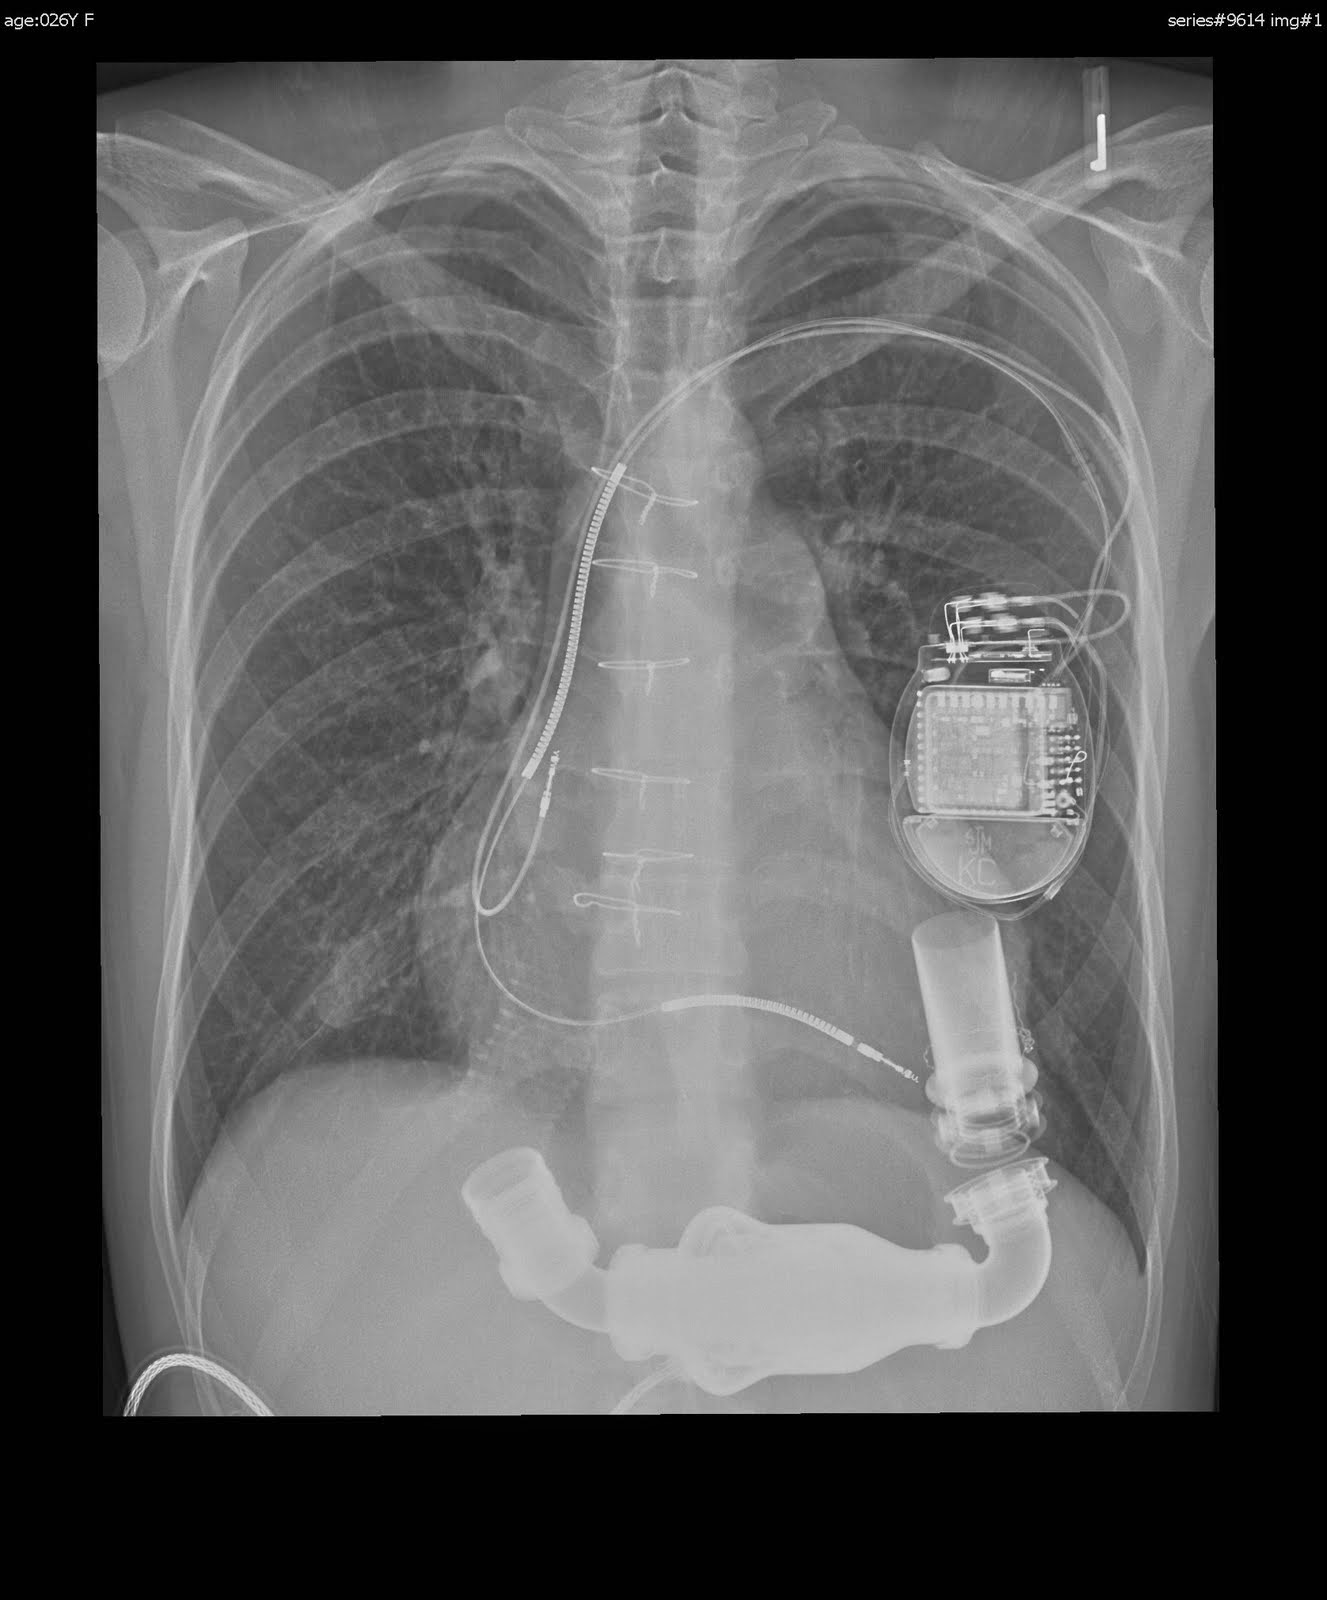

第1位 Masa、7月からTransplant & MCS Fellowship @ THI開始!!

- 心肺同時移植手術

- Total Artificial Heart移植手術